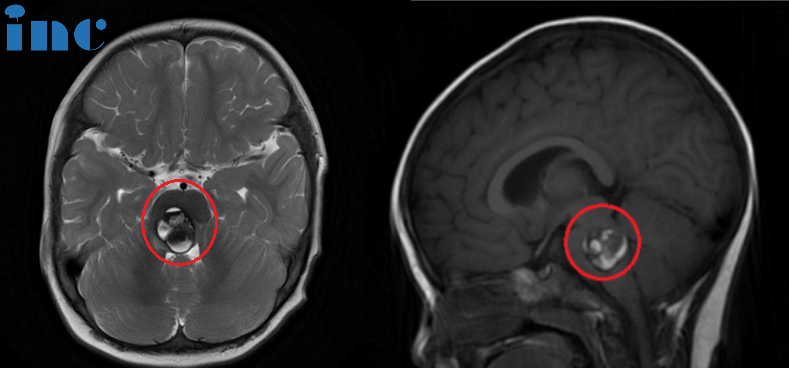

脑海绵状血管瘤的本质是一团结构畸形的血管,不是一团需要被...